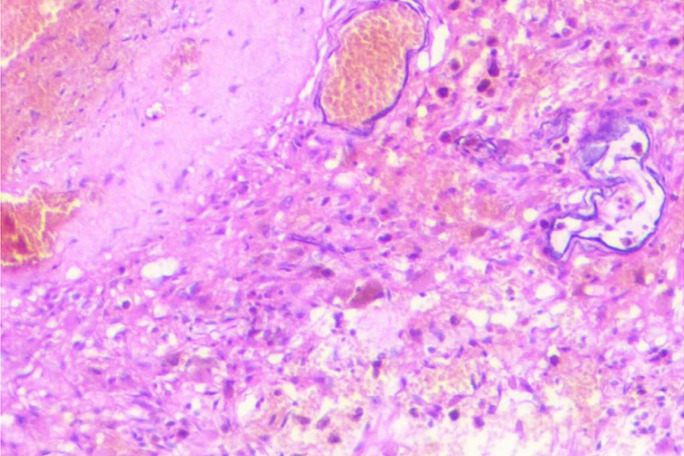

儿童巨大小脑海绵状瘤非常罕见,必须与出血性小脑肿瘤区分开来。巨型小脑海绵状瘤的诊断和治疗具有挑战性,但完全的手术切除可带来良好的结果,大多数病例的神经功能可完全恢复。我们报告了一例八个月大的婴儿,他被诊断出患有巨大海绵状瘤,导致继发性梗阻性脑积水,并伴有神经精神症状。患者接受了枕骨下入路的副颅骨开颅手术,完全切除了海绵瘤。经过九个月的观察,患儿的行走能力有所改善,神经系统也完全康复。我们还进行了文献综述,确定了包括本病例在内的 11 例儿童巨大小脑海绵状瘤病例。我们对这些数据进行了分析,以确定儿童巨大小脑海绵状瘤的临床特征、治疗方法和结果。

Giant cerebellar cavernomas in children are rare and must be differentiated from hemorrhagic cerebellar tumors. The diagnosis and treatment of giant cerebellar cavernomas is challenging, but complete surgical resection can lead to favorable outcomes and complete neurological recovery in most cases. We present a case of eight months old baby who was diagnosed with a giant cavernoma resulting in secondary obstructive hydrocephalus with neuropsychiatric presentations. The patient underwent a paramedian craniotomy surgery with a suboccipital approach and complete surgical resection of the cavernoma was done. Over nine months of observation, the child showed improvement in their ability to walk and fully recovered from a neurological perspective. We also conducted a literature review to identify eleven cases of giant cerebellar cavernomas in children, including our case. The data were analyzed to determine the clinical features, treatment, and outcomes of giant cerebellar cavernomas in children.